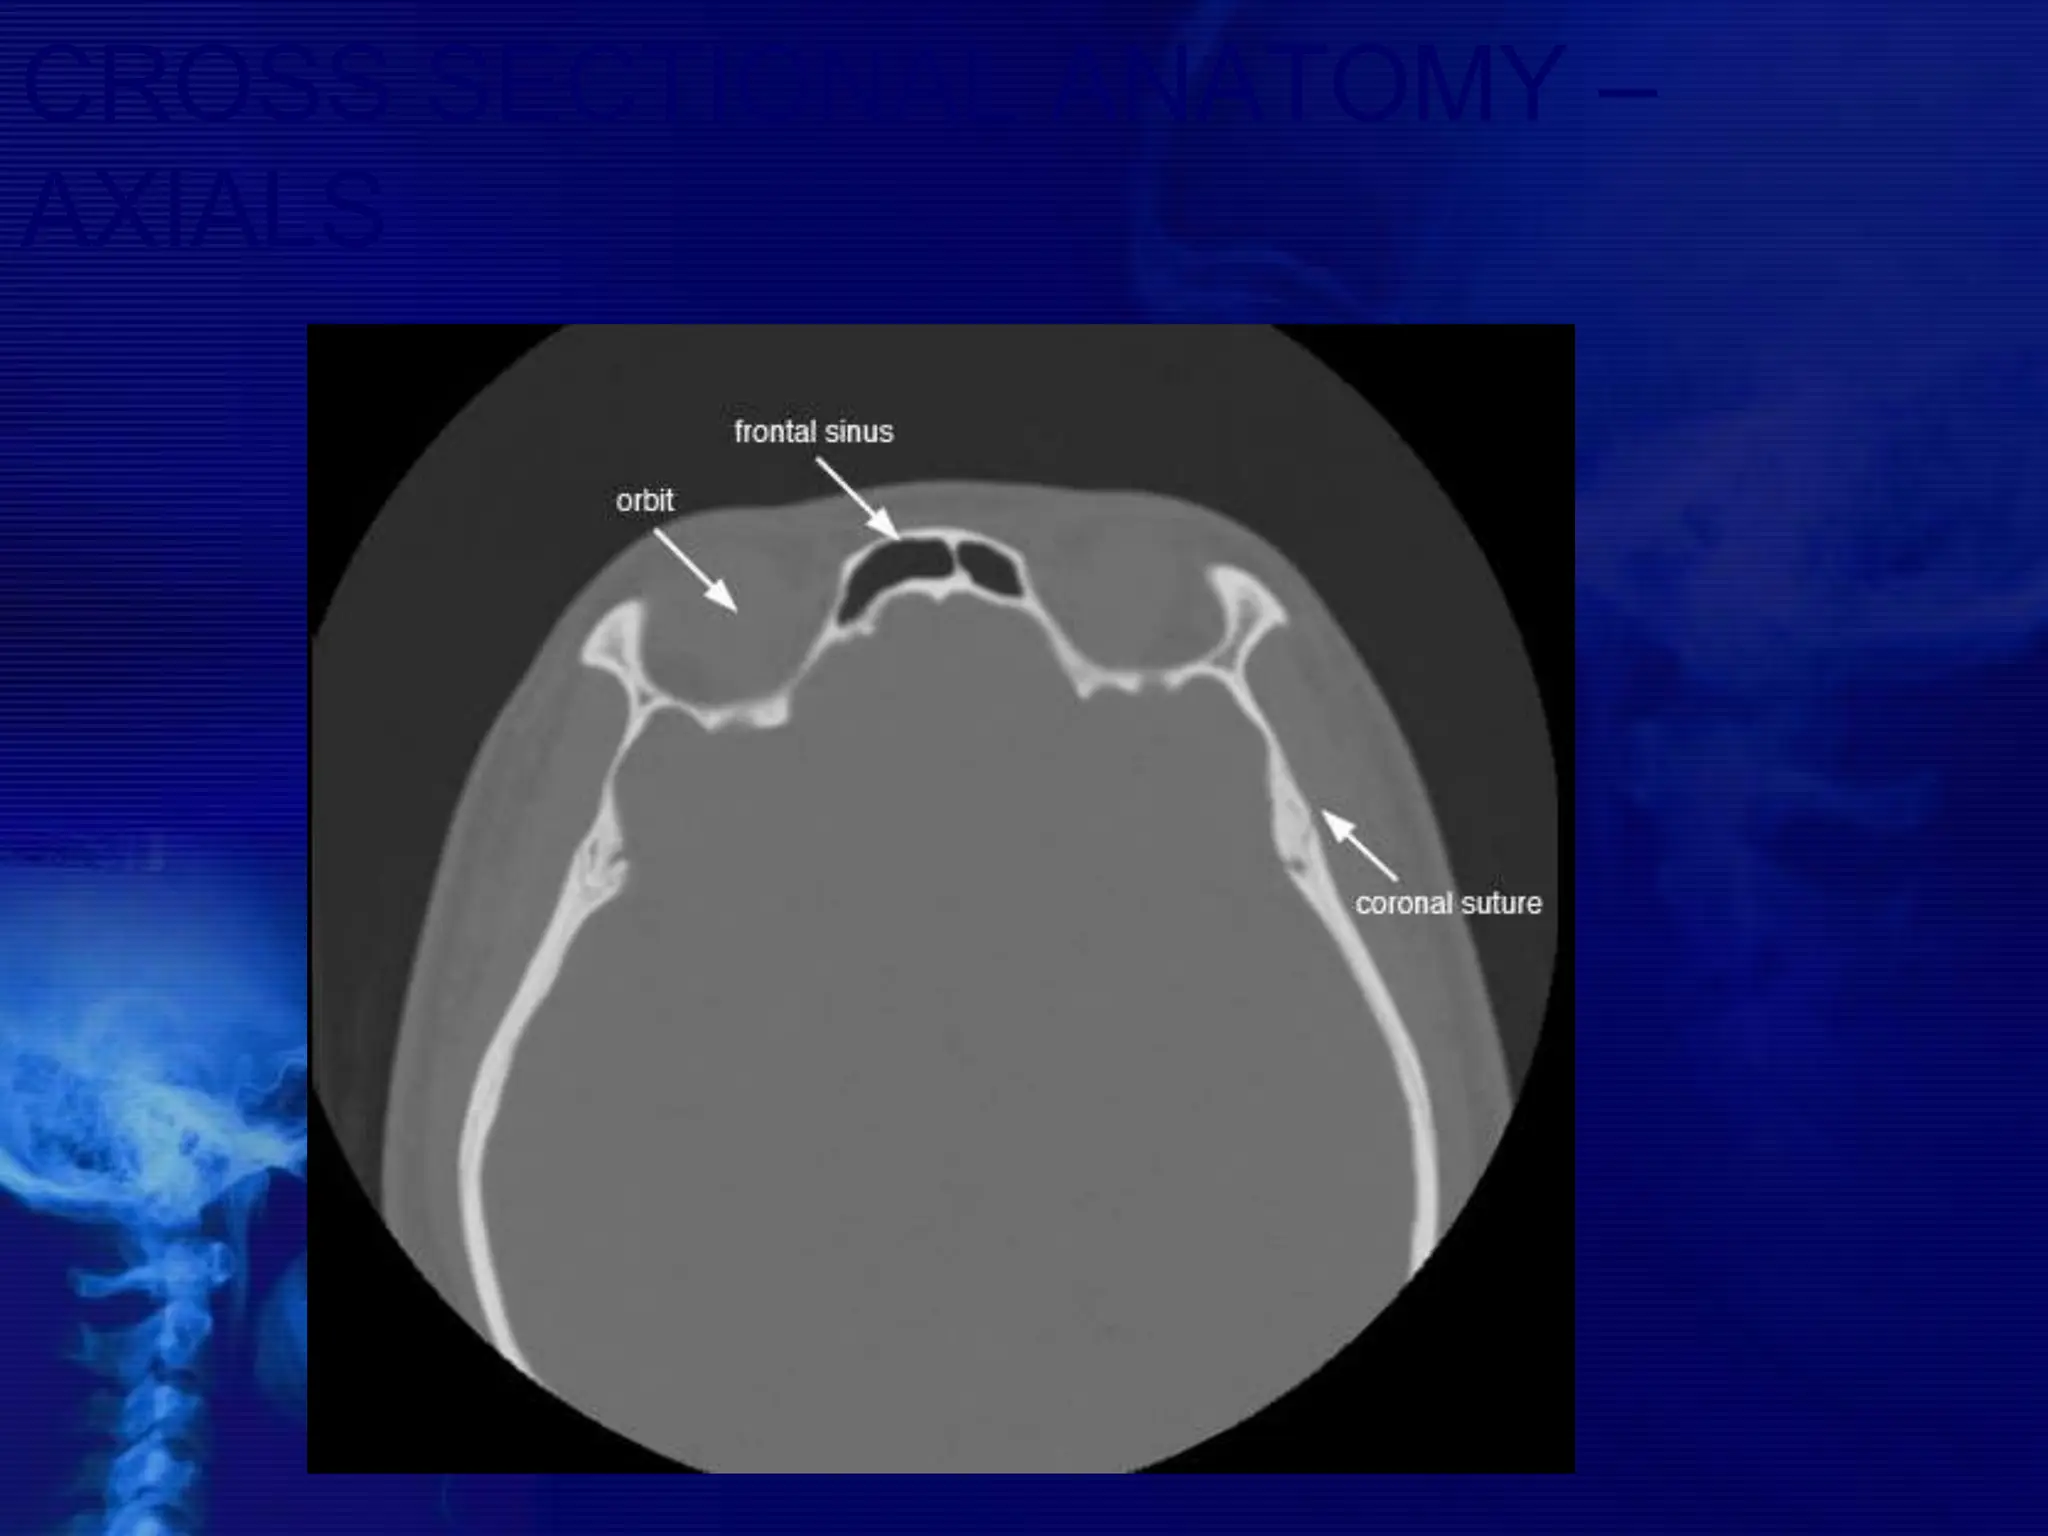

CROSS SECTIONAL ANATOMY –

AXIALS

BASIC CONCEPTS • CTscans typically obtained for visualizing the paranasal sinus should include coronal and axial (3- mm) cross sections.  Soft tissue and bony windows facilitate evaluation of disease processes and the bony architecture.  The use of intravenous contrast material just prior to scanning can help define soft tissue lesions and delineate vascularized structures, such as vascular tumors.  Contrast-enhanced CT is particularly useful in evaluating neoplastic, chronic, and inflammatory processes.

 The CTscan is the GOLD STANDARD investigation in all preoperative cases as it gives detailed bony anatomy of the area and serves as a ‘road map’ for the operating surgeon.  CT scans are best done after a course of antibiotics, so that acute inflammation is not mistaken for chronic mucosal disease.